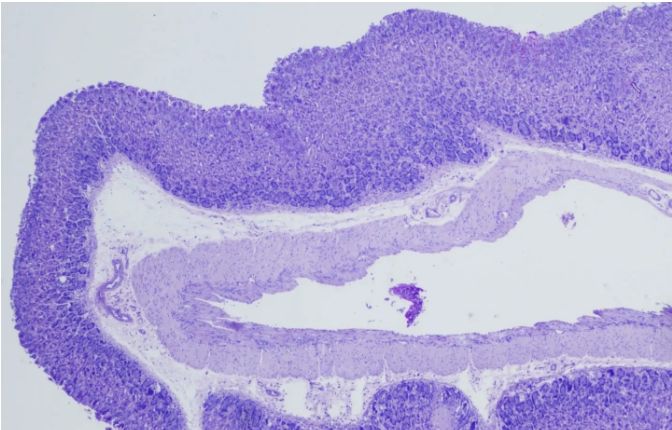

二、細胞類型和結構

PAS染色不僅可以顯示多糖類物質,還可以揭示細胞的類型和結構。例如,在某些病理狀態下,某些細胞可能會過度分泌多糖類物質,導致染色結果異常。通過觀察這些細胞的形態和分布,我們可以進一步了解疾病的發病機制和進展過程。

三、與其他染色的比較

在解讀PAS染色結果時,我們還可以將其與其他染色方法進行比較。例如,與HE染色相比,PAS染色能夠更直觀地顯示多糖類物質的分布和含量;而與免疫組化染色相比,PAS染色則具有更高的特異性和敏感性。通過比較不同染色方法的結果,我們可以更全面地了解組織的結構和功能狀態。

HE染色

八月瓜果皮PAS染色